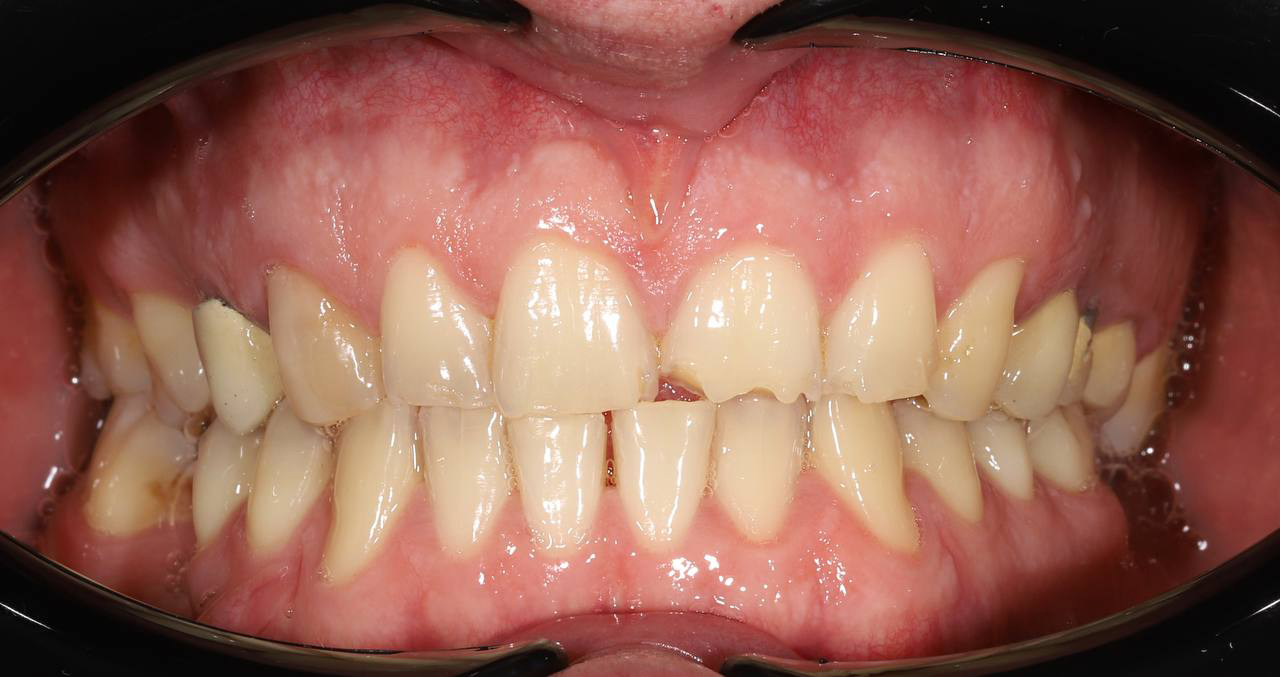

Ортодонтическое лечение с генерализованным пародонтитом